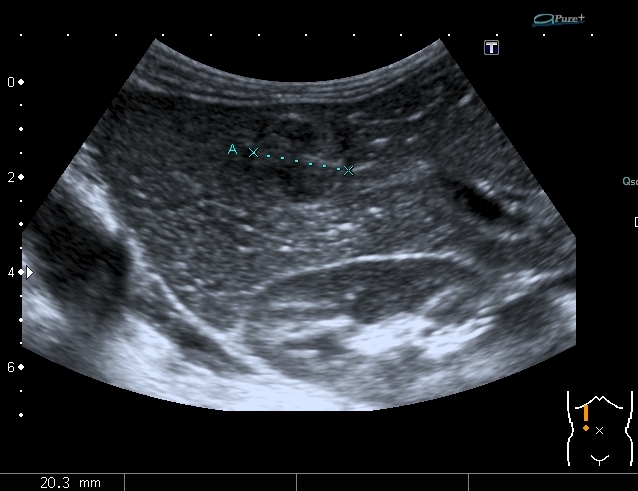

Предлагаю интересные изображения, полученные при сканировании лёгких через межрёберные промежутки и печень у ребёнка 4-х лет с подозрением на пневмонию

Добавляю сканы печени, я думаю они являются хорошей подсказкой о природе изменений в лёгких

Левая доля печени

Она же